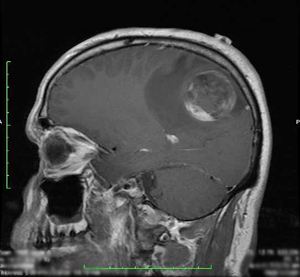

Type of Cancer: Grade III Anaplastic Ependymoma

The day I was told I had a 4.3 cm tumor in my head was as if someone had tossed on top of me a hundred lead blankets, the kind you wear during x-rays at the dentist. It was a train wreck of epic magnitude. But I quickly decided I would do my best to get the train back on the rails. Since the initial chaos I have endured three surgeries, radiation and chemotherapy.